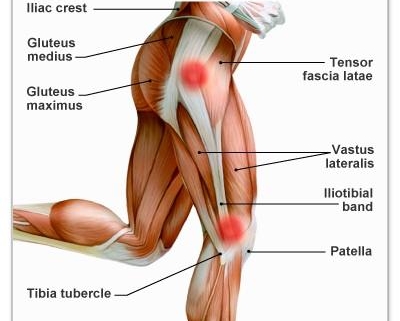

Iliotibial Band Syndrome (ITBS) is a common type of knee injury often seen in runners, cyclists, and hiking enthusiasts. The Iliotibial Band, a thick piece of connective tissue, runs from the hip down to the shin. When this tissue becomes inflamed, tight or irritated, it can result in pain and discomfort, generally referred to as ITBS.

The most defining symptom of ITBS is a stinging sensation on the outer part of the knee, particularly during or after physical activity. Additional symptoms may include: